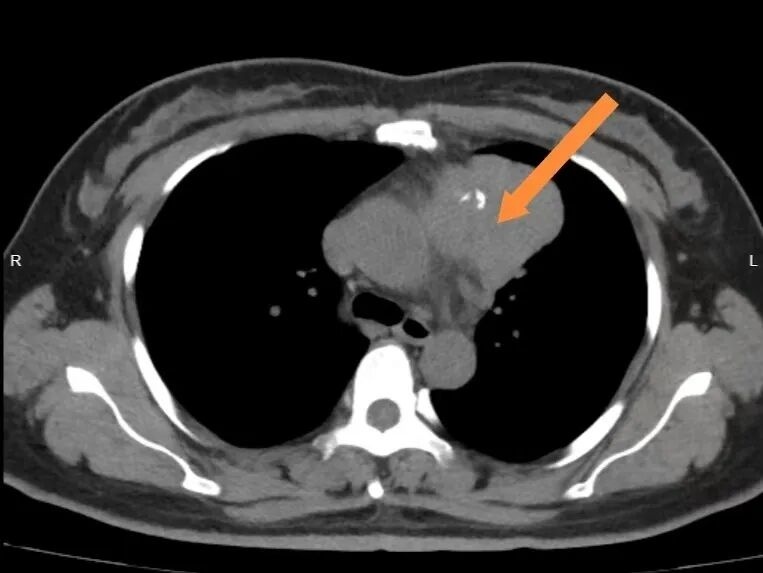

心里犯嘀咕的王阿姨当天就去当地医院检查,胸部CT结果让她一惊:纵隔长了一个直径约6.7厘米的肿块,已经压迫到周围组织。但她平时生活中一点异样的感觉都没有。

想着拳头大的肿块长在胸口,当时腿都软了!”在亲戚的建议下,王阿姨从老家赶到宁波寻求进一步治疗。接诊的宁波市医疗中心李惠利医院胸外科应健健副主任医师仔细评估后明确:这纵隔肿块是胸腺肿瘤,并且大概率为恶性胸腺瘤,已侵犯周围肺组织,压迫大血管。而王阿姨的“杵状指”,正是肿瘤压迫肺组织,以及生长过程中产生的一些物质导致手指末端血管、组织增生的典型表现

“纵隔里密集分布着心脏、大血管、气管,这个肿块像‘埋’在重要器官中间,手术既要切除肿瘤,又得避开关键结构。”应健健医疗团队反复研讨后,确定了微创剑突下切口下的“胸腺扩大切除术+肺部分切除术”方案——既完整切除胸腺肿瘤、受侵肺组织,最大程度保留肺功能,又避免了正中胸骨劈开带来的巨大创伤。